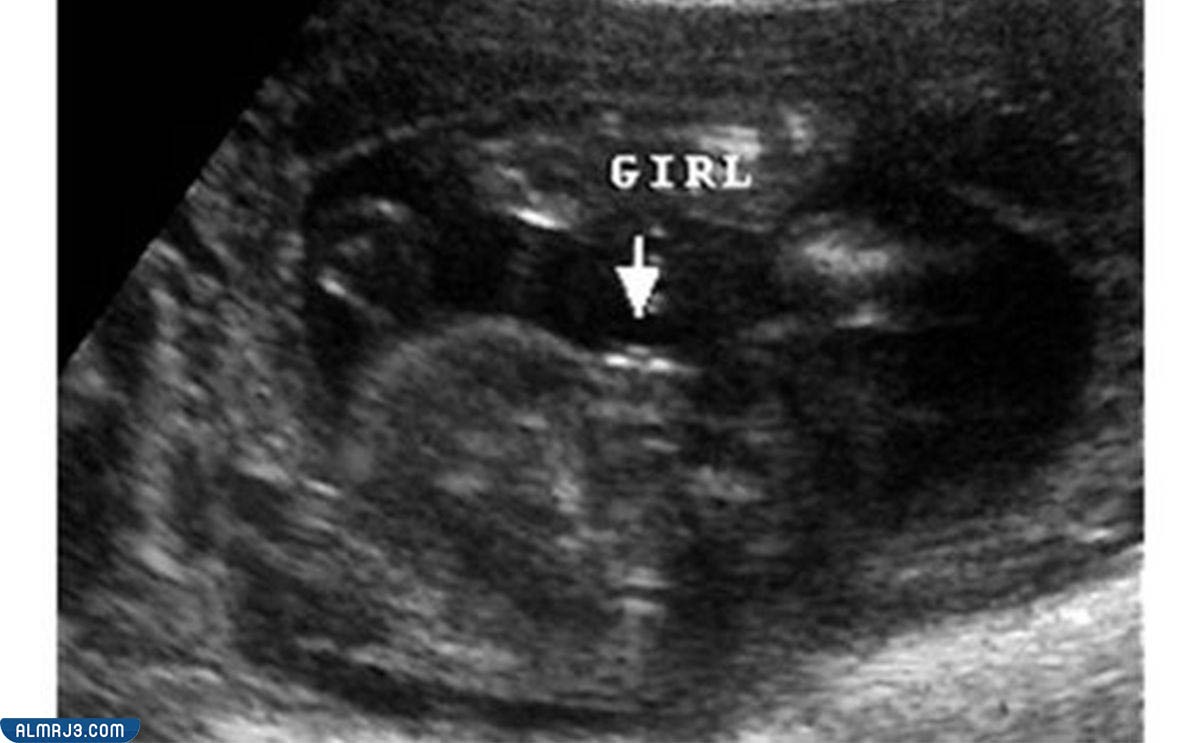

يكون شكل الجنين واضح ومميز في أجهزة السونار بداية من الشهر الرابع من الحمل، ولكنه ويزداد وضوحًا كلما اقتراب موعد الولادة، وبشكل عام يمكن تحديد شكل الجنين البنت من خلال فحص الأعضاء التناسلية الخاصة، إذ تملك الجنين البنت شفرتين، وذلك بالإضافة إلى العضو التناسلي، والذي يستطيع طبيب النساء المتخصص من تحديده بمنتهى السهولة، فتتشابه الأعضاء التناسلية الخاصة بالجنين البنت إلى حد كبير مع شكل الهمبورجر.[1]

وفي الشهر الرابع من الحمل يمر الجنين بالعديد من التغيرات، والتي يستطيع الطبيب ملاحظتها داخل أجهزة السونار بمنتهى السهولة، وذلك مع تكون كل من الجلد والأعضاء التناسلية، فستكون لدى الجنين البنت شفرتان، وذلك إلى جانب العضو التناسلي الخاص بها، والذي يمكن رؤيته بسهولة في حال كانت تأخذ الجنين البنت وضعية مناسبة لذلك الأمر.

- الجنين الأنثى في السونار: يُصعب تحديد الجنين الأنثى من قِبل العديد من الأطباء نتيجة صغر العضو التناسلي الخاص، ولكن يمكن تحديده مع التقدم في شهور الحمل خاصة وأنه يتشابه مع الشطيرة الصغيرة المكونة من طبقتين وهما الشفرتان.